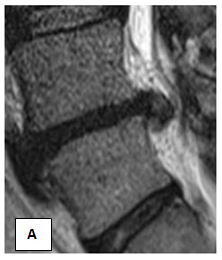

Patient C, 31 years old. Has acted with complaints on sharp pains in a loin, pulling pains in the left leg, numbness of the left leg, paresthesia. When examining antalgic scoliosis to the left, weakness in the right n / extremity, it’s shortening by 1.5cm, with Lassega s sharply positive on the right. MRI (ris.5-6) Disc L 4-5: moderate decrease in disc height and intensity MR - signal. Op. posterior median disc hernia with left lateralization of 17* 7.9* 7.9mm, with a tendency to sequestration (Figures 3A & 3B).

Figure 3 Patient C, before treatment.